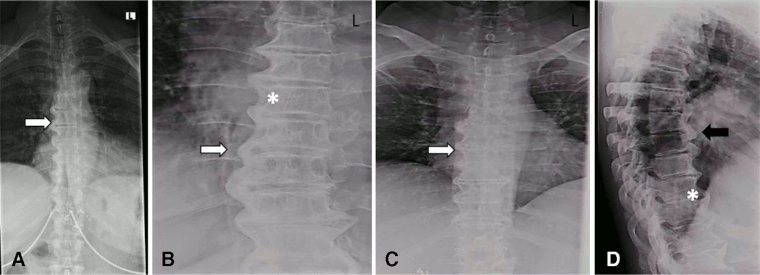

Spine radiography is the cornerstone of the diagnosis of DISH, although DISH is often an incidental finding during routine imaging.[1]

The osteophytes of DISH are most likely to be seen on the right anterior thoracic spine, directly across from the pulsating aorta.[1]

Look for coarse, thick osteophytes that develop mostly on the right side and horizontally along the anterior longitudinal ligament.[4] These findings are often described as having a 'flowing candle wax' appearance. 'Flowing' osteophytes, at a minimum of 3-4 contiguous vertebrae, are a distinguishing feature of DISH.[34][38][39][40]

Other characteristic diagnostic features include preservation of disc height and lack of significant degenerative changes at the involved vertebral segments, as well as absence of ankylosis at the facet-joint interface and absence of sacroiliac joint erosion, sclerosis, or fusion.[34]

[Figure caption and citation for the preceding image starts]: X-ray images of the thoracic spine of a patient with DISH. (A–C) Posterior–anterior and (D) lateral: large right-sided flowing bridges (white arrows). Note the space between the ligament and the vertebral body (*). Thick flowing ossification of the anterior lateral ligament is shown (black arrow)Mader R, et al. RMD Open 2020; 6: e001151. doi: 10.1136; used with permission [Citation ends].

may reveal presence of coarse, thick osteophytes often on the right side and horizontally along the anterior longitudinal ligament, with a 'flowing candle wax' appearance; may reveal preservation of disc height and lack of significant degenerative changes at the involved vertebral segments, absence of ankylosis at the facet-joint interface, and absence of sacroiliac joint erosion, sclerosis, or fusion